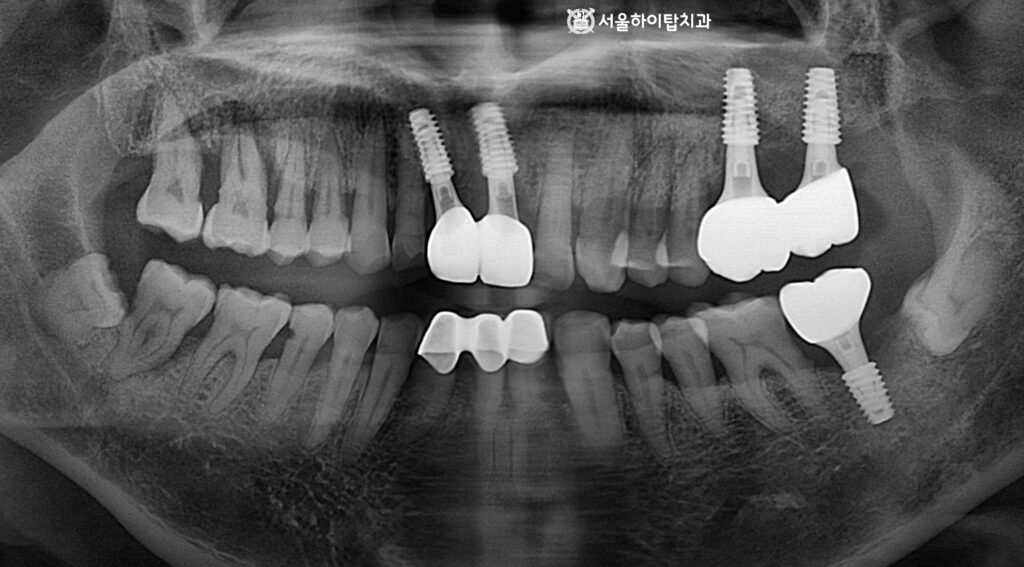

1. 초진

간석역 치과 에서는

한눈에 보더라도 상, 하악 어금니가

상실된 모습을 확인할 수 있습니다.

특히 위턱 부위의 치조골이

상당히 흡수된 모습이 관찰되며,

이는 장기간 기능을 하지 못한 치아

부위에서 흔히 나타나는 변화입니다.

6. 최종 결과

인상채득을 통해 맞춤형 보철,

지르코니아 크라운이 제작되어

연결된 모습입니다.

이를 통해 저작 기능과 심미성이

한층 더 향상된 상태임을

확인할 수 있습니다.

무엇보다 이제 균등한 저작을 통해

치아와 보철에 가해지는 힘이

고르게 분산되어,

치아 구조의 안정성이 높아지며,

편측 저작도 개선됩니다.